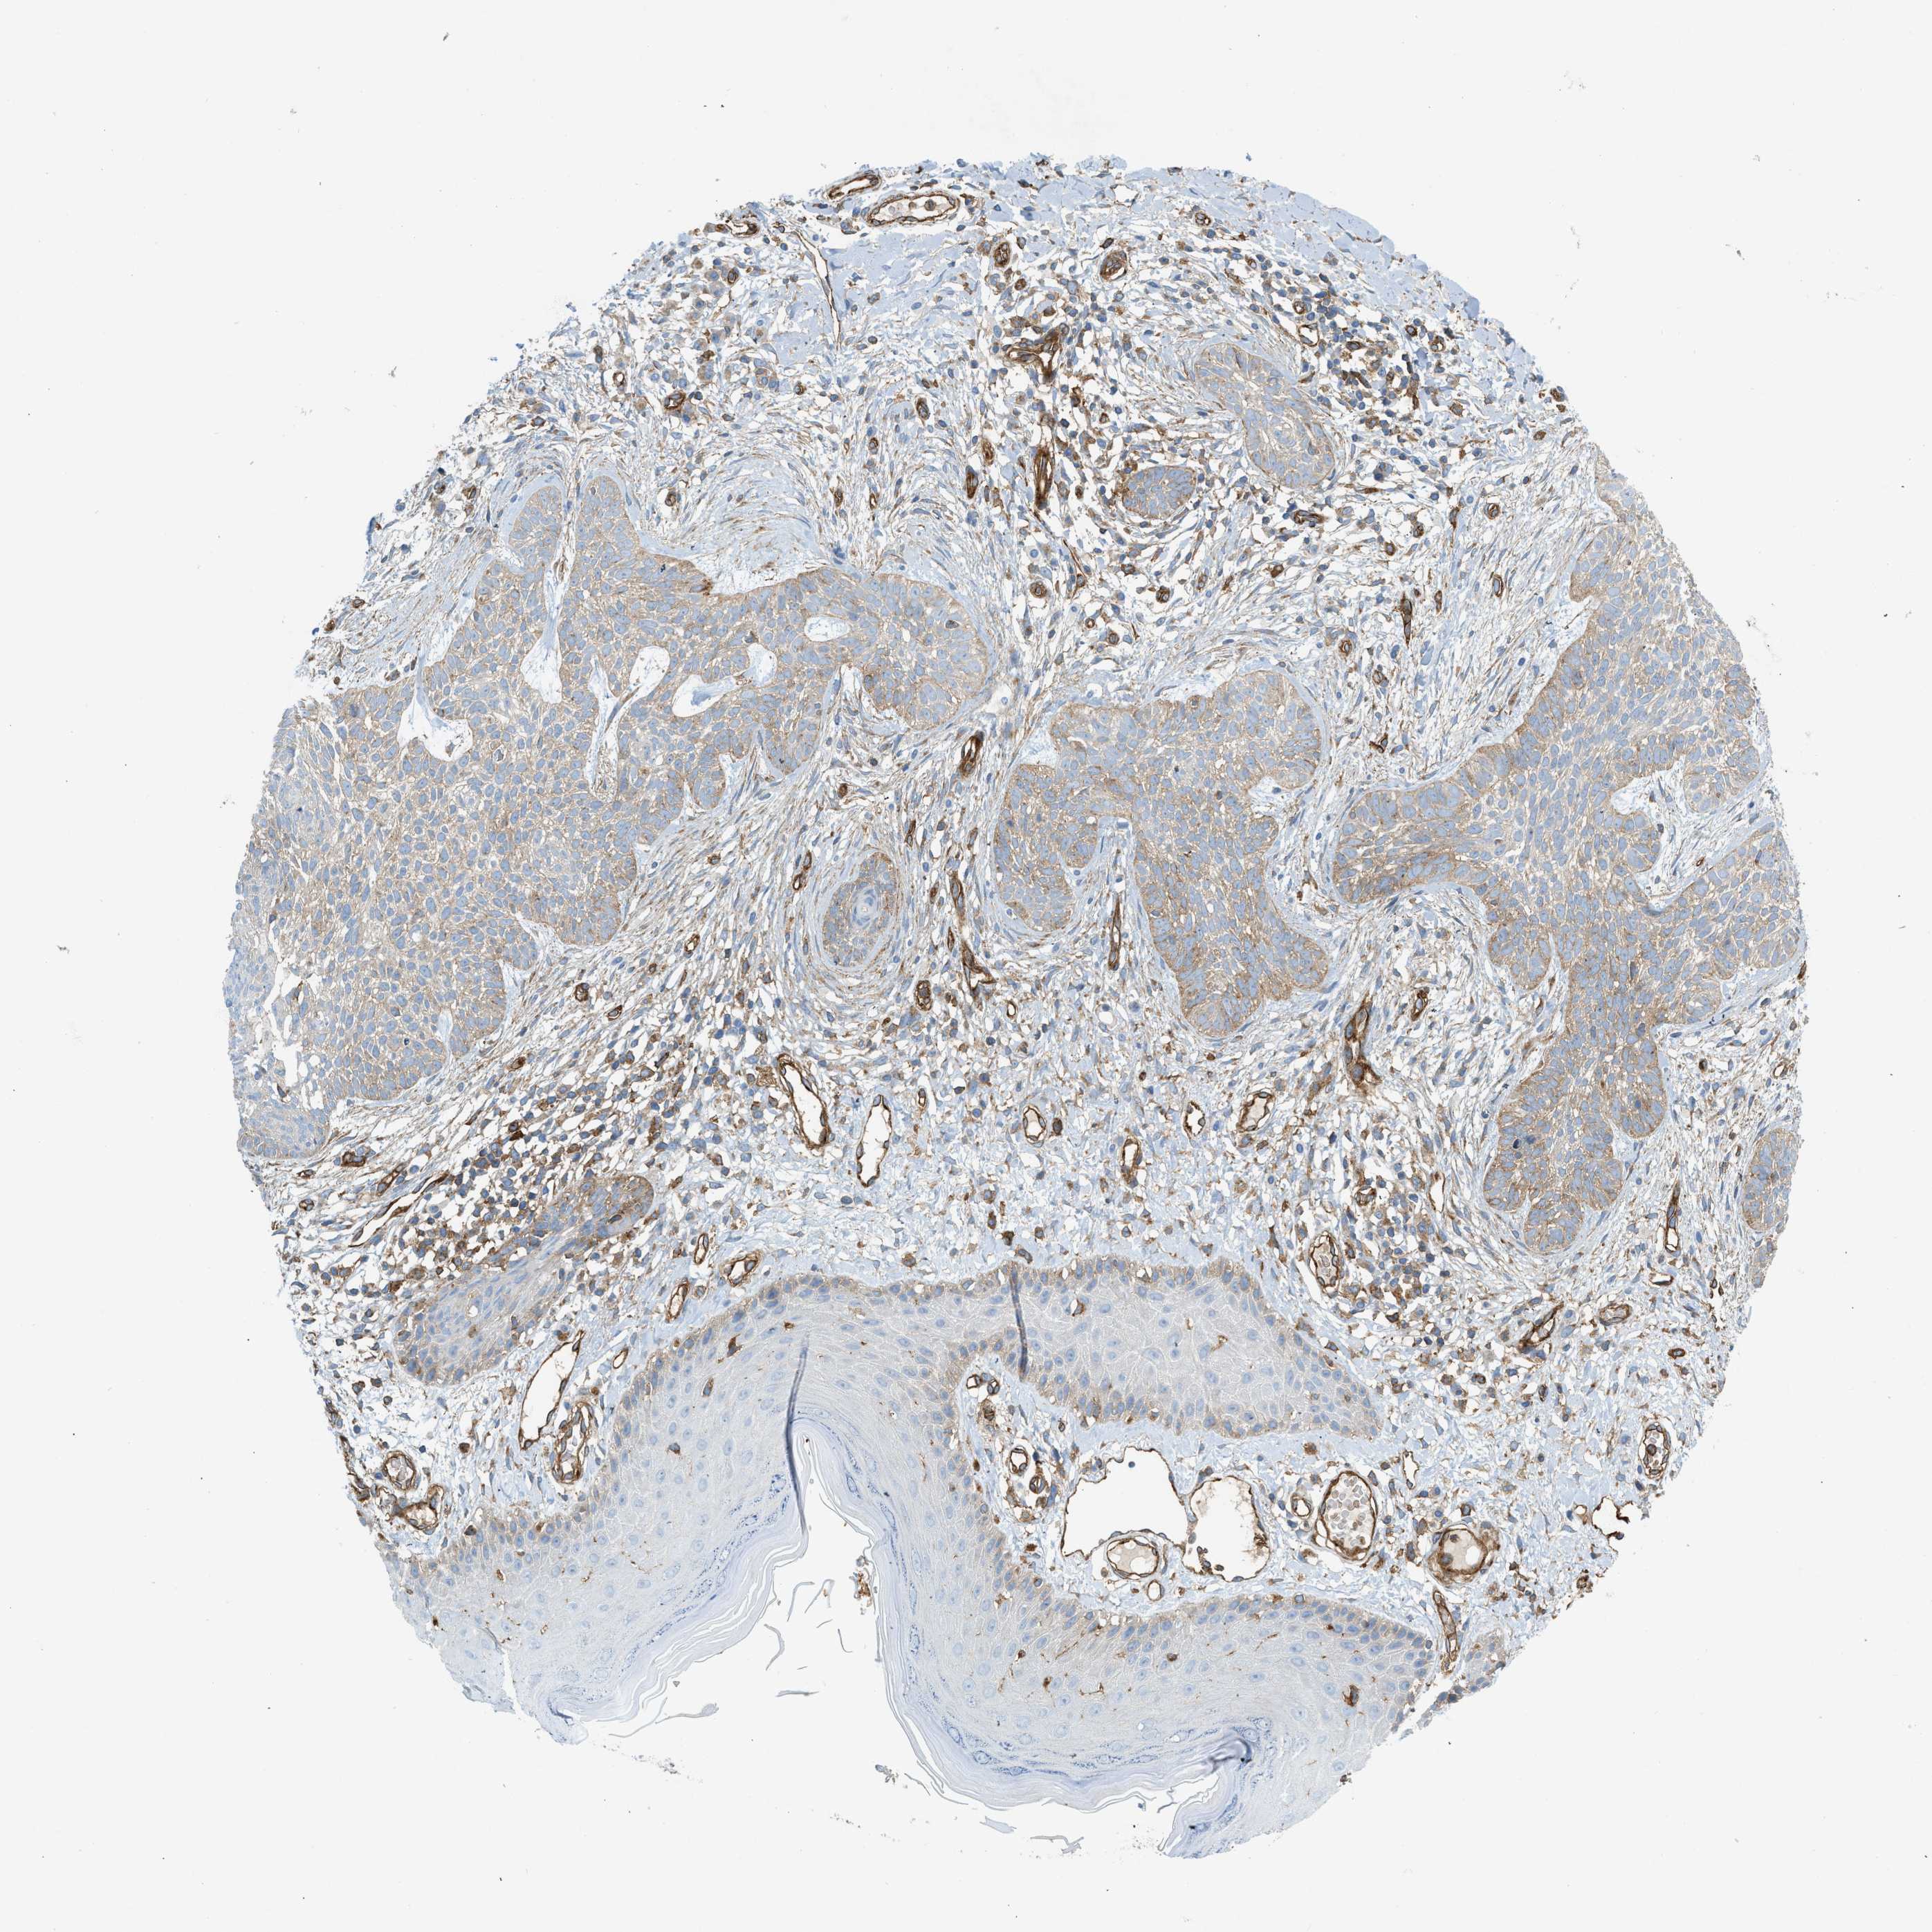

SKIN CANCER - Protein expressioni

A mouse-over function shows sample information and annotation data. Click on an image to view it in a full screen mode. Samples can be filtered based on level of antibody staining by selecting one or several of the following categories: high, medium, low and not detected. The assay and annotation is described here.

Each image is clickable and will lead to virtual microscopy that enables deeper exploration of all samples and also displays staining intensity scores, fraction scores and subcellular localization as well as patient and tissue information for each sample.

Antibody CAB016402

Staining

High

Medium

Low

Not detected

Intensity

Strong

Moderate

Weak

Negative

Quantity

>75%

75%-25%

<25%

None

Location

Nuclear

Cytoplasmic/membranous

Cytoplasmic/membranous,nuclear

Squamous cell carcinoma in situ, NOS

Squamous cell carcinoma, NOS

Squamous cell carcinoma, metastatic, NOS

Basal cell carcinoma

Adnexal tumor, benign